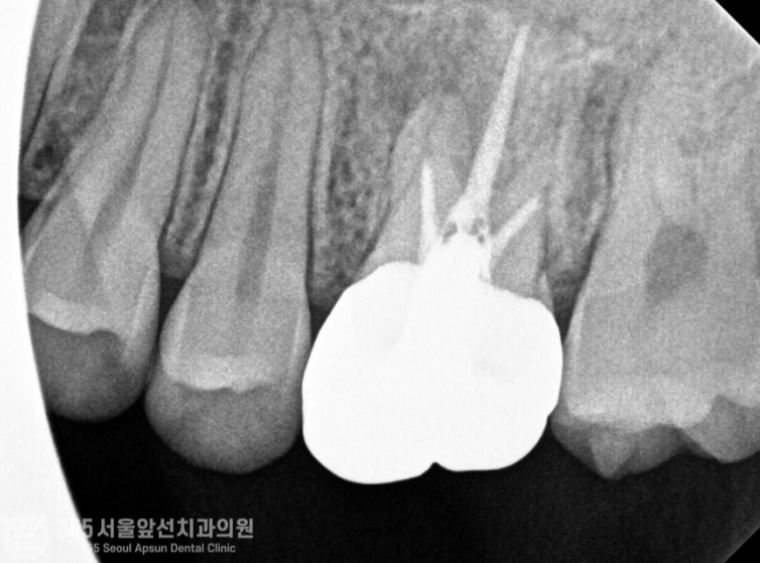

안녕하세요. 미추홀구치과 365서울앞선치과의원입니다. 오늘은 재신경치료 증례를 살펴보겠습니다. 왼쪽 위쪽의 치아가 아프다는 불편감으로 환자분께서 내원하셨습니다. 너무 아파서 잠을 제대로 못 주무셨다고 하십니다. 수면부족으로 많이 예민해지신 상태셨습니다 ㅠㅠ 구강 내를 관찰하며 검사를 시작합니다. "아~ 해보세요" 전반적으로 깨끗한 상태셨지만 기존에 치료받았던 치아가 통증의 원인으로 의심이 되는 상황입니다. 촬영일시 : 2024.06.21. 내원 당시 파노라마 엑스레인 사진입니다. 자세하고 정확한 검사를 위해 작은 엑스레이 사진을 한장 촬영했습니다. 촬영일시 : 2024.06.21. 과거 타병원에서 신경치료 및 크라운 치료를 받으신게 관찰됩니다. 과거 신경치료를 받으셨던 치아 뿌리 끝에 염증이 생겼네요 ㅠㅠ 신경치료의 충전 상태가 짧은 것도 관찰됩니다. 이런 경우, 환자분의 나이 및 건강상태 그리고 치아의 치료상태 등을 종합적으로 판단하여 치아를 보존할지 아니면 발치하고 임플란트로 계획을 세울지 결정해야합니다. 해당 치아의 경우 치아의 상태는 좋지 않았지만 기존 신경치료의 충전 상태가 그다지 좋지 않은 상황이라 재신경치료를 통해 한 번 더 치아를 살려서 써보는 것이 가능한 상황으로 보였습니다. 하지만 재신경치료의 경우 일반적인 신경치료에 비해 난이도가 높고 성공율이 떨어지는 것도 사실입니다. 그만큼 최선을 다해도 쉽지 않은 것이 재신경치료인데요~ 다행히 위 환자분께서는 성공적으로 재신경치료를 마무리할 수 있었습니다 ㅎㅎ 촬영일시 : 2024.06.21. 재신경 치료를 통해 깔끔하게 충전된 모습이 엑스레이상에서 관찰됩니다. 쉽지 않은 치료도 최선을 다하는 마음을 갖는다면 좋은 결과를 얻을 수 있다는 것을 느끼게 해준 증례였습니다. 오늘도 감사합니다 항상 최선을 다하는 치과의사가 되겠습니다 ^^ [ 치료기간: 2024년 6월21일 ] ※ 365서울앞선치과의원의 모든 포스팅은 각 진료과 의료진이 직접 작성합니다. 365서울앞선치과의원 블로그의 임상 케이스 게시물은 환자분께 의학적으로 정확하고 상세한 정보를 드리기 위해 각 진료과 의료진이 직접 작성하며, 모든 증례 사진은 본원 의료진이 직접 시술한 증례를 촬영한 것으로, 의료법 제23조, 제56조에 의거하며 환자분의 동의를 얻어 포스팅에 사용하였습니다. 또한 해당 케이스는 본 환자분의 치료 결과이며, 환자 상태에 따라 치료의 결과는 달라질 수 있습니다. |